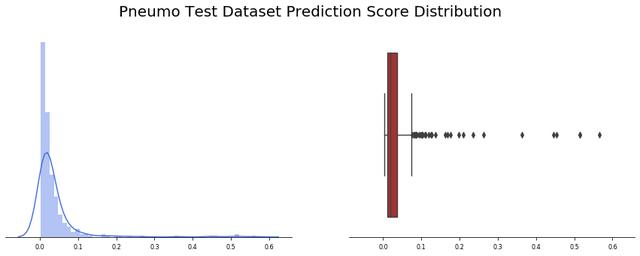

我们观察了234张诊断为正常的“未公开”图片(还有390张不是由Covid-19引起的肺炎)。应用批处理函数,我们观察到24幅图像出现假阳性(约10%)。让我们看看模型输出值是如何分布的,记住函数返回的值计算如下:

pred = new_model.predict(image)pred_pos = round(pred[0][0] * 100)

我们观察到,预测精度的平均值为0.15,并且非常集中于接近于零的值(中值仅为0.043),有趣的是,大多数误报率接近0.5,少数异常值高于0.6。

我们对390张标记为非Covid-19引起的肺炎的图像应用批测试功能,我们发现总共390张图片中只有3张出现假阳性(约0.8%),此外预测精度值的平均值为0.04,并且非常集中于接近于零的值(中值仅为0.02)。

总的结果甚至比以前的模型所观察到的还要好,有趣的是,几乎所有的结果都在前3个四分位之内,只有很少的异常值有超过20%的误差。